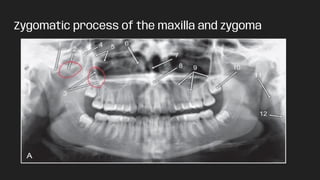

Zygomatic process of the maxilla and zygoma

Zygomatic process ofthe maxilla and zygoma